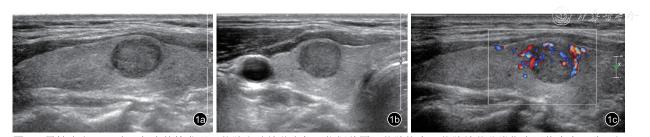

81例患者的甲状腺结节ATA低度、中度和高度可疑恶性分别为2例(2.5%)、28例(34.5%)(图1)和51例(63.0%);ACR-TIRADS 3类、4类和5类分别为2例(2.5%)、31例(38.3%)和48例(59.2%);C-TIRADS 3类、4A类、4B类、4C类和5类分别为2例(2.5%)、7例(8.6%)、11例(13.6%)、11例(13.6%)和50例(61.7%)。

图1 男性患者,51岁,超声体检发现甲状腺右叶结节半年,依据美国甲状腺协会甲状腺结节分类指南评价为中风险;行超声引导下甲状腺细针抽吸活检:符合甲状腺髓样癌,免疫组织化学检测结果:Calcitonin(+),癌胚抗原(+),甲状腺转录因子1(+),Thy(散在+),CgA(+),Syn(+);术后病理结果:甲状腺髓样癌(直径1.5 cm)。图a:甲状腺纵切面声像图;图b:甲状腺横切面声像图示右叶实性结节,大小1.2 cm×1.1 cm×1.1 cm,呈低回声,形态尚规则,边界尚清;图c:彩色多普勒血流显像示甲状腺结节周边及内部较血流信号丰富